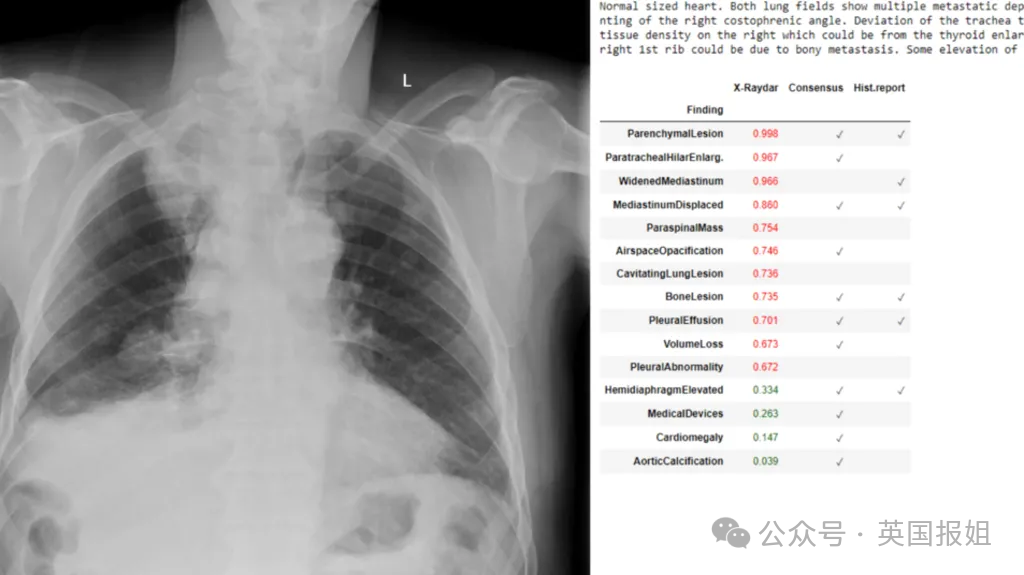

比如,去年12月英国华威大学发布的一项研究称,AI可以像医生一样分析X光片并诊断医疗问题。

项目的AI算法使用超过150万名患者的胸部X光片进行了训练,分析37种可能出现的病症。其中的35种与医生的分析同样准确,某些情况下准确率甚至超过了医生。

当然,研究人员提到类似AI项目的目的不是要代替医生,而是减少医生的工作量和诊断延误,为放射科医生提供“第二意见”。